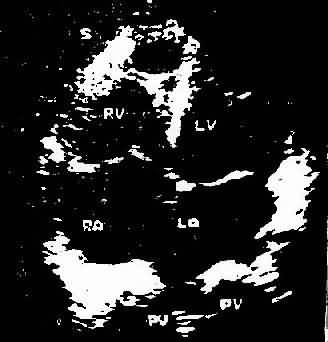

此是利用超声扫描技术 在荧光屏上显示超声波通过心脏各层结构如;心包、心肌、心内膜、室间隔、瓣膜和主动脉时发生的反射,借以观察心脏与大血管的搏动情况、房室的舒张和瓣膜开关的活动规律。目前常用的M型、B型超声心动图对二尖瓣、主动脉瓣的狭窄和关闭不全、三尖瓣狭窄,二尖瓣脱垂,特发性肥厚性主动脉瓣下狭窄,心房粘液瘤,心包积液,房、室间隔缺损等的诊断均有较大的价值。此外,利用超声心动图测量房、室腔的大小,计算心排出量、射血分数等以了解左心室功能。近年来应用彩色多普勒血流显像探查瓣膜关闭不全的返流和先心病的分流量、提高了疾病诊断质量。(图3-1-4图3-1-5)

图3-1-5 心尖四腔心切面二维超声心动图

A、照片 B、示意图